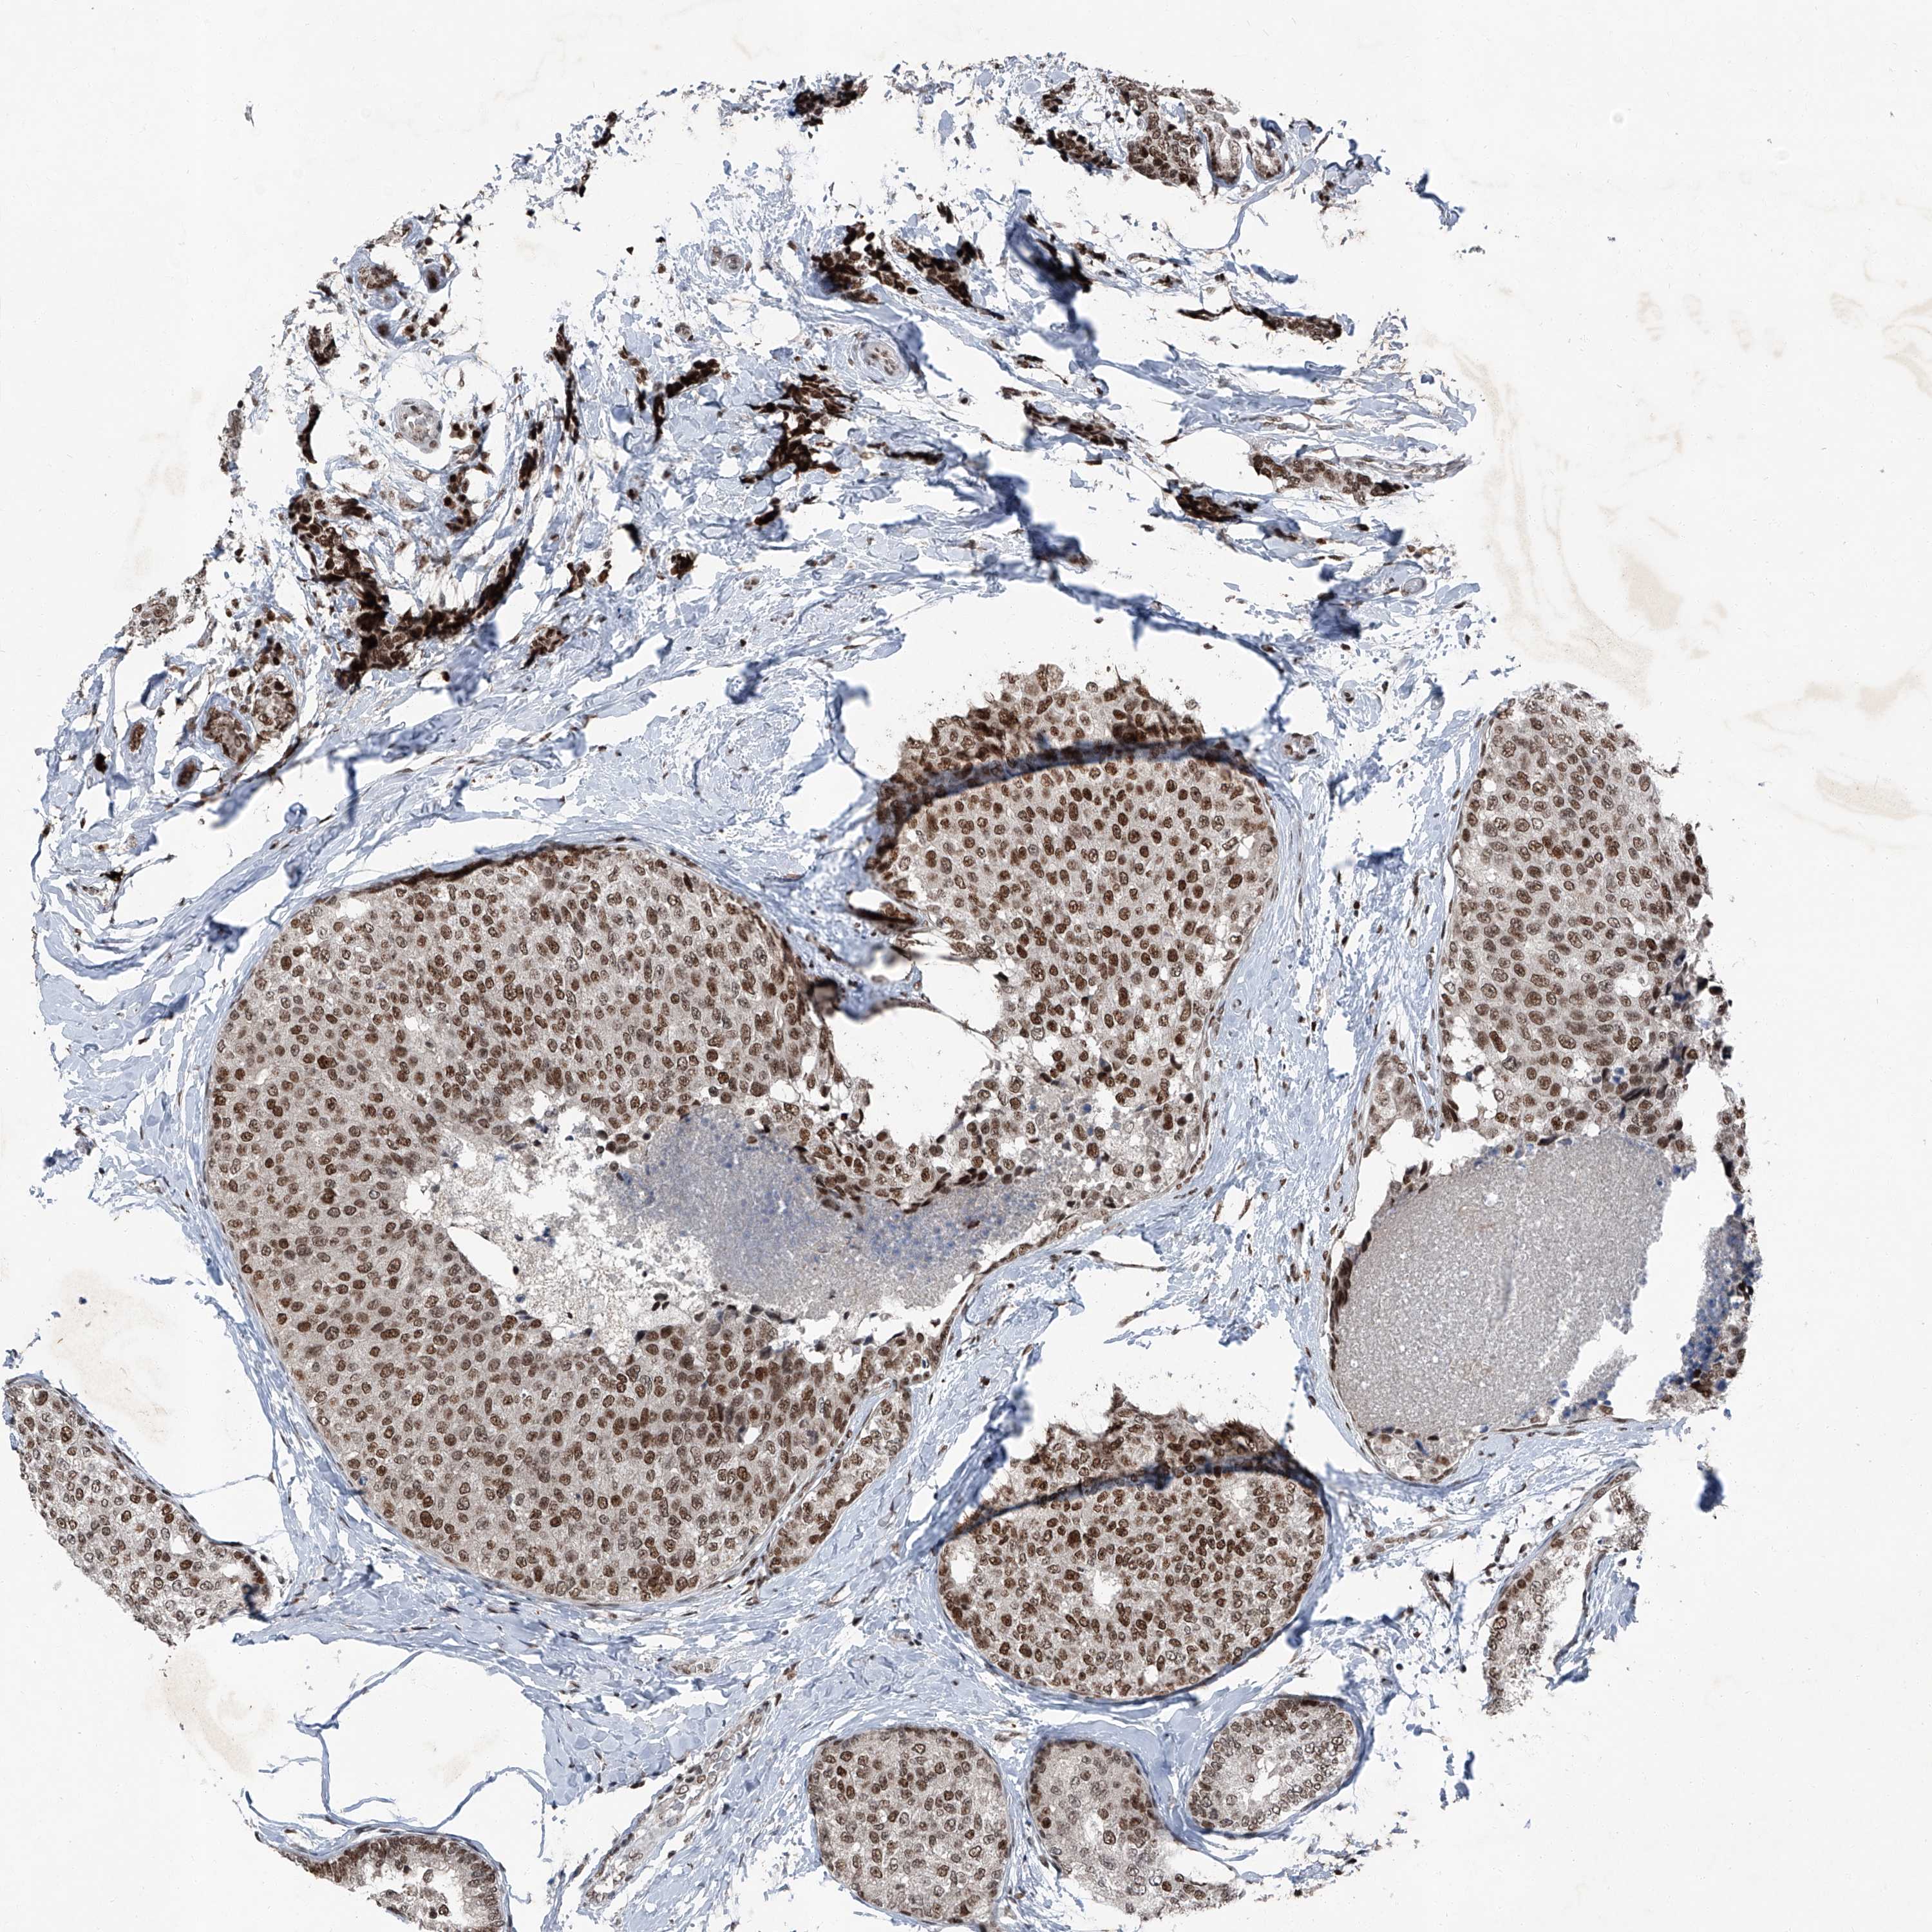

BRCA TCGA BRCA VALIDATION PROTEIN EXPRESSION

ANTIBODIES

AND

VALIDATION